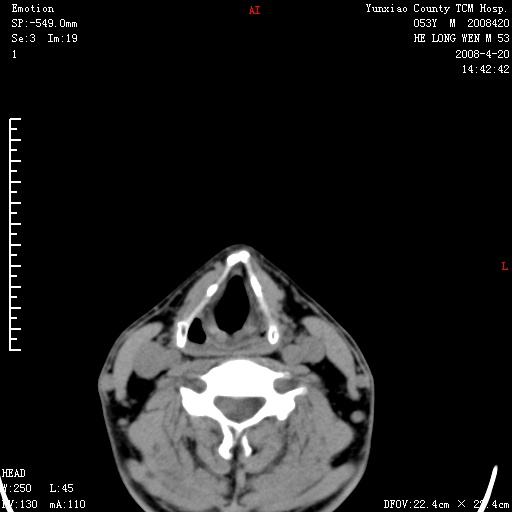

双侧扁桃体肿大:考虑化脓性扁桃体炎。

双侧扁桃体肿大 ,考虑扁桃体炎。

双侧扁桃体肿大,建议结合临床!

双侧扁桃体肿大 ,考虑扁桃体炎

应该有症状,体检此部位不是常规体检项目,支持双侧扁桃体肿大 ,考虑扁桃体炎,但还是强化一下吧。

双侧扁桃体肿大,考虑扁桃体炎,应做一下增强

显示部分为舌扁桃体,腭扁桃体未见显示。会厌显示欠规则,建议喉镜。